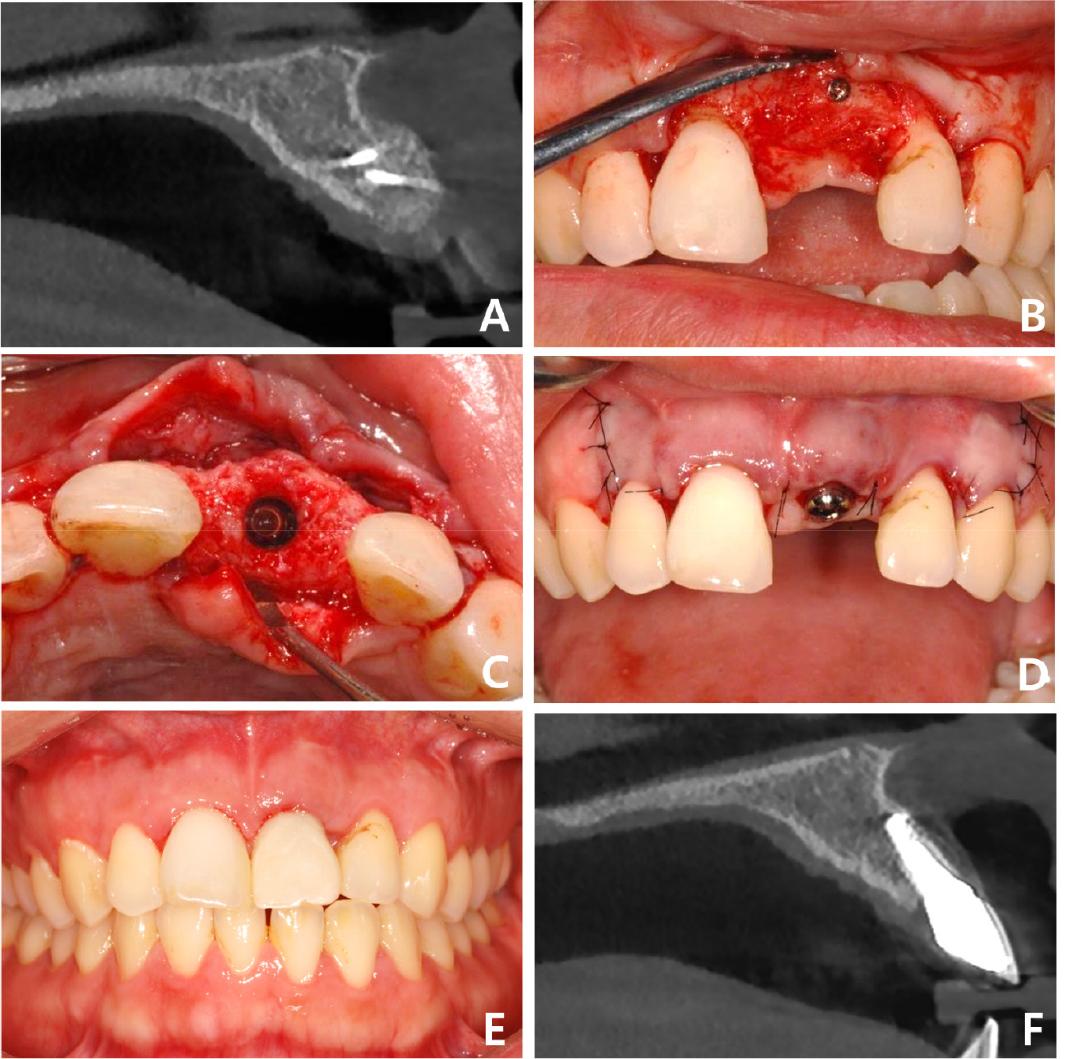

Fig. 3.

Case 1: Intraoral photos of allogeneic block-bone graft surgery. (A) Occlusal view before grafting, (B) Frontal view before grafting, (C) Allogeneic bone block has been grafted on the labial side in the #21 region, (D) A collagen membrane has been applied over the bone block for separation from the soft tissue.

Regular follow-up was performed during the bone remodeling phase of approximately four months, and the stability of the graft was confirmed using CBCT (Fig. 4A). The fixation microscrews were removed, and an implant was placed at the graft site (Fig. 4B). A bone-level implant (IU; Warantec, Seongnam, Korea) with a tapered body, diameter of 4.0 mm, and length of 10.0 mm was used (Fig. 4C). The initial fixation torque was 25 Ncm, and a healing abutment was connected to the implant (Fig. 4D). Three months after implant placement, provisional restoration was performed with soft tissue alterations. The final prosthesis was fabricated and the patient was satisfied with the new central incisor (Fig. 4E). At the 4-year follow-up, CBCT revealed a decrease in the grafted bone volume; however, the final implant prosthesis was intact (Fig. 4F).

Fig. 4.

Case 1: Intraoral and radiographic views related to implant placement and final prosthesis at the grafted site. (A) Sagittal CBCT image of the grafted site before implantation, (B) Frontal view after flap elevation for implantation, (C) Occlusal view of augmented site after implantation, (D) Frontal view after healing abutment connection, (E) Frontal view after final prosthesis delivery, (F) Sagittal CBCT image of the implant prosthesis at the four-year follow-up. CBCT, cone-beam computed tomography.